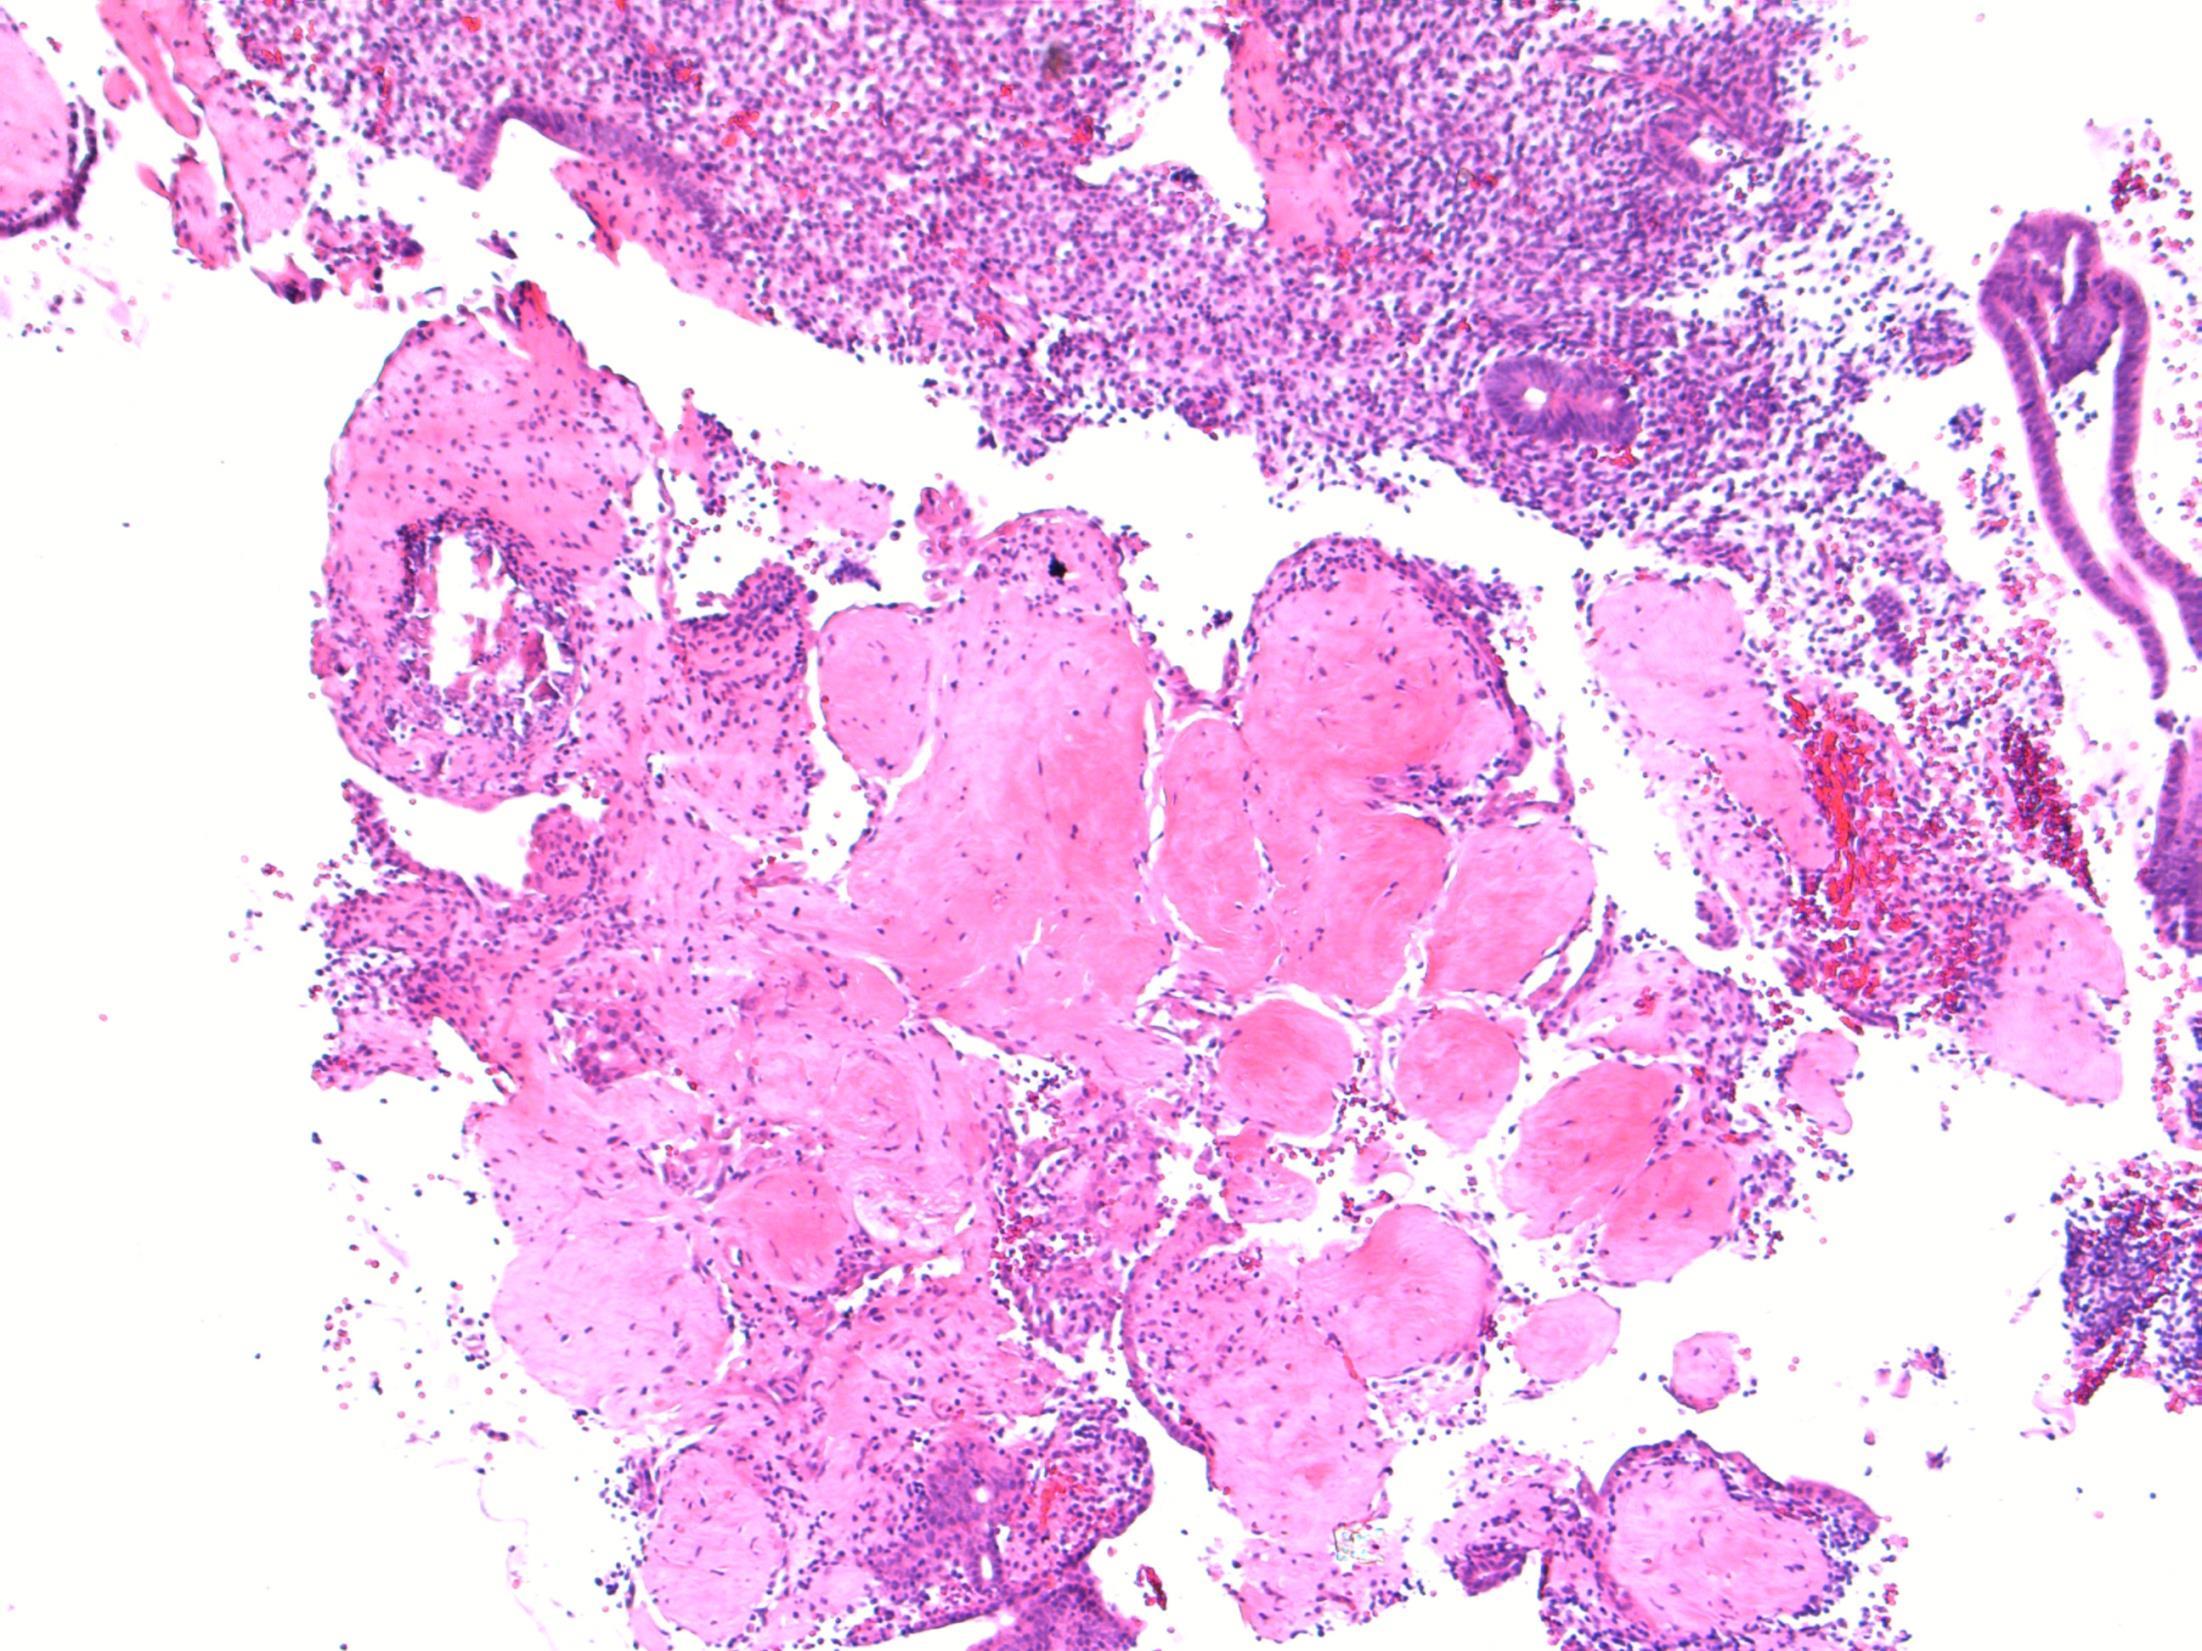

Description: Abrupt transition between tumour and epithelium. Plump papillary invaginations of thickened and infolding epithelium, hyperkeratosis. Lack of cytological atypia, suprabasal mitoses. Retraction of normal epithelium at margin. Diagnosis: Verrucous carcinoma Differential Diagnosis:

Conventional SCC – cellular atypia • Squamous papilloma – more exophtyic & branching, less keratin • Reactive inflammatory epithelial hyperplasia – most difficult but rete pegs more slender and anastomosing; no mitoses; macro correlation Plan: Correlate with previous biopsies ( often quite bland so can be inconlusive) Examine further blocks for worse areas and measure margins. Comments: In head and neck – oral cavity and larynx Often large, locally aggressive, pushing margin Better prognosis than SCC